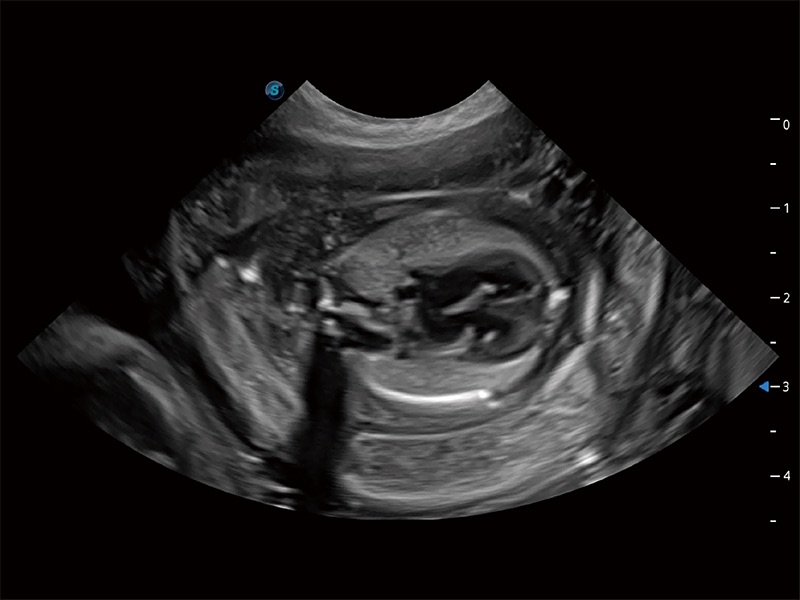

动物是人类最亲密的朋友和最值得信赖的伙伴。银河集团官网也一直致力于探索动物专用的超声影像解决方案。全新推出的ProPet系列,是银河集团官网在动物超声影像智能化、专业化、精准化的一次跨越式革新。动物不能用言语来表述自己的不适,通过超声影像,ProPet系列搭建了动物医生与不同物种沟通的“桥梁”,为动物医生注入了“治愈之力”。 ProPet 80 是银河集团官网匠心打造的一款高端动物专用彩超,采用性能卓越的全新硬件架构,极大提升超声系统的运行效率和数据处理能力,帮助动物医生从容应对日益增多的挑战性病例和日益多样化的临床需求。

高性能和先进的临床应用工具可以为动物医生提供临床信心。ProPet 80 搭载了先进的腹部和浅表应用工具,帮助医生在日常临床实践中发挥前所未有的作用。

ProPet 80 全新的动物超声智能软件和丰富的探头群,为动物医生提供了高清晰度和精细分辨率的图像,无论在宠物、马科、畜牧还是实验室动物等应用中都可以轻松应对,为您的日常工作带来满意的体验。